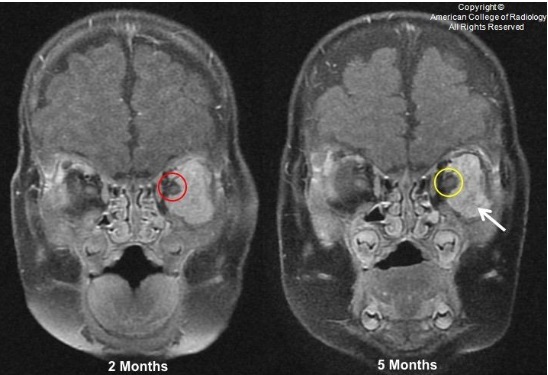

图 7 为患者 2 个月和 5 个月时分别随访 MR,可见眶骨膜和眼球间的组织间隙存在(红色箭头)。可见血管流空信号(黄色箭头)

图 8 为患者 2 个月和 5 个月时分别随访 MR,可见眶骨膜和眼球间的组织间隙存在(红色箭头)。可见血管流空信号(黄色箭头)。此外,T2 上病变部分区域信号变得不均匀(白色箭头),表明有退行性的纤维化和脂肪化

图 9 为患者 2 个月和 5 个月时分别随访 MR,可见肿块包绕视神经程度减轻,从 270°(红色圈)减少到 180°(黄色圈)。增强扫描后肿块强化变得不均匀(白色箭头),表明有退行性的纤维和脂肪组织